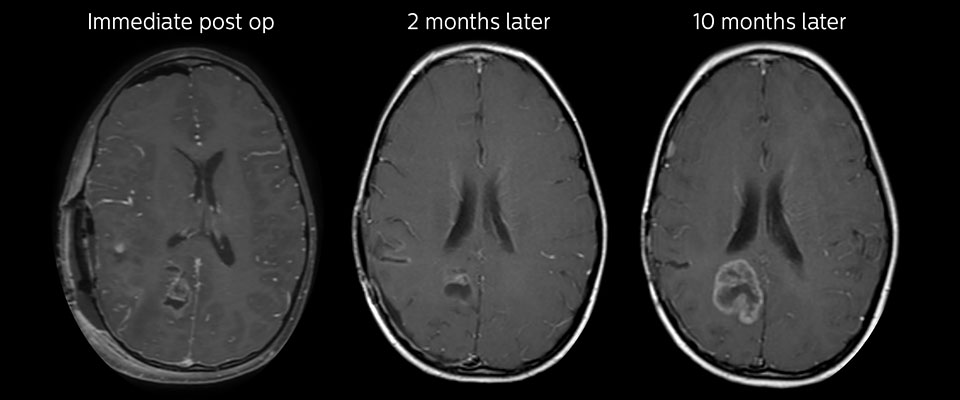

APT may illuminate post-resection images with crucial information

MRI may be performed after tumor resection, to look for residual tumor or tumor regrowth. Also here, the different contrast mechanism of APT may help in diagnosis. Dr. Miller remembers a particular case. “After a very good resection, we saw small changes on the postcontrast T1-weighted and the T2-weighted images that looked like a post-surgical little bit of fluid. Interestingly, however, we saw a focal area of APT signal, right in the center of that abnormality. As we usually do when a bit unsure, we followed it up and, unfortunately, found tumor regrowth in that region,” Dr. Miller says. “Cases like this motivate me, and others who care about this population, to investigate how this APT method could be used on large scale in this population and help us in providing high value diagnostic information.” The hospital’s physicians also saw a case where APT had a negative predictive value. Following the resection of a highgrade tumor, they saw a similar small change in the images of this patient. However in this case, the APT signal was rather low. In a recent rescanning of this patient, no recurrence was seen.

MRI with APT post resection

Immediately post resection MRI was again performed. T2-weighted and postcontrast T1-weighted images are quite inconclusive for distinguishing residual tumor tissue from postoperative tissue changes. On the APT image some high signal is still seen, which would suggest residual tumor tissue.

Follow-up over time

In later follow-up scans the post-contrast T1-weighted images suggest recurrent tumor growth. So, it would be interesting to study the predictive value of APT in a large patient group.